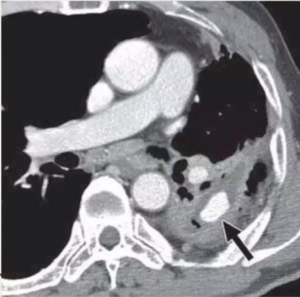

CECT show tuberculous nodes that show central areas of low attenuation suggestive of caseous necrosis and peripheral rim enhancement.

CECT obtained shows cavitatory consolidation with air-crescent sign in left upper lobe.